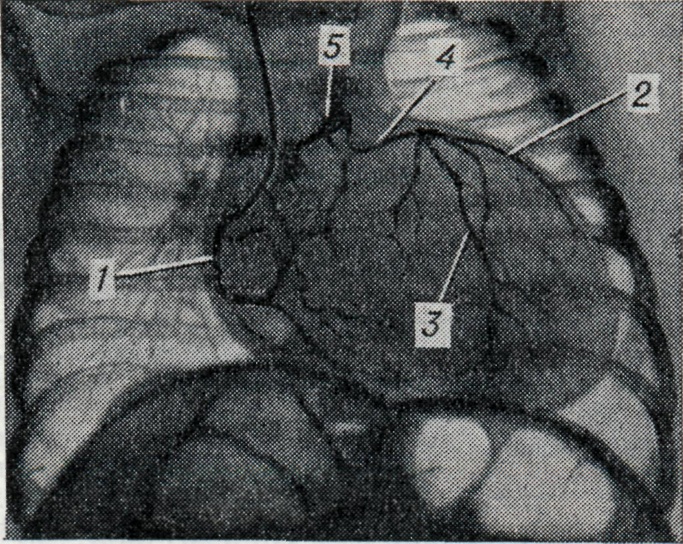

Для точного распознавания этой аномалии необходима полуселективная или селективная коронарография отходящего от аорты сосуда. При коронарографии (см.) обычно обнаруживается мощная коронарная артерия, после контрастирования к-рой отмечается ретроградное контрастирование вначале дистальных, а затем центральных отделов другой артерии и, наконец, при достаточном сбросе крови — легочного ствола (рис.). При отхождении основных коронарных артерий от аорты и аномальном отхождении добавочной артерии от легочного ствола (чаще конусной) феномен его ретроградного контрастирования наблюдается обычно при селективной коронарографии левой артерии.

Рис.

Селективная коронарограмма (прямая проекция) ребенка двух месяцев с синдромом Бланда — Уайта — Гарленда. После контрастирования правой венечной артерии (1) контрастируются огибающая (2) и передняя мешшелудочковая (3) ветви левой коронарной артерии и ее ствол (4) (катетер в правой венечной артерии). Видно пристеночное контрастирование легочного ствола (5).